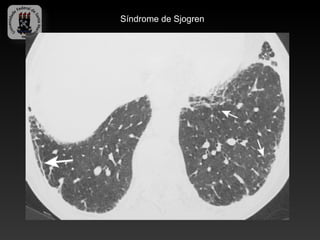

-SÍNDROME DE SJOGREN

-Caracterizada: ceratoconjuntivite seca, xerostomia e desordens do tecido

conjuntivo.

-Manifestações pulmonare: fibrose intersticial, doenças de pequenas vias

aéreas, PIL, linfoma MALT.

-Achados TC (PIL):

-   Atenuação em vidro fosco

-   Lesões císticas

-   Nódulos centrolobulares

-   Espessamento intersticial

Síndrome de Sjogren

Síndrome de Sjogren - PIL